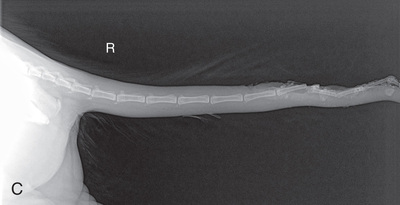

MEASURE: Thickest part of the tail.

CENTRAL RAY: Area of interest.

BORDERS: Four or five vertebrae on either side of the area of interest, or the full tail.